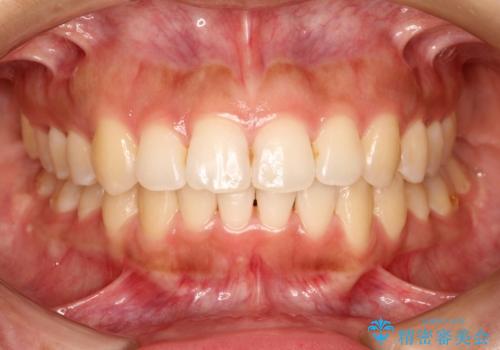

[ インビザライン ]飛び出た前歯を抜かずに矯正治療

担当医 大元洋佑